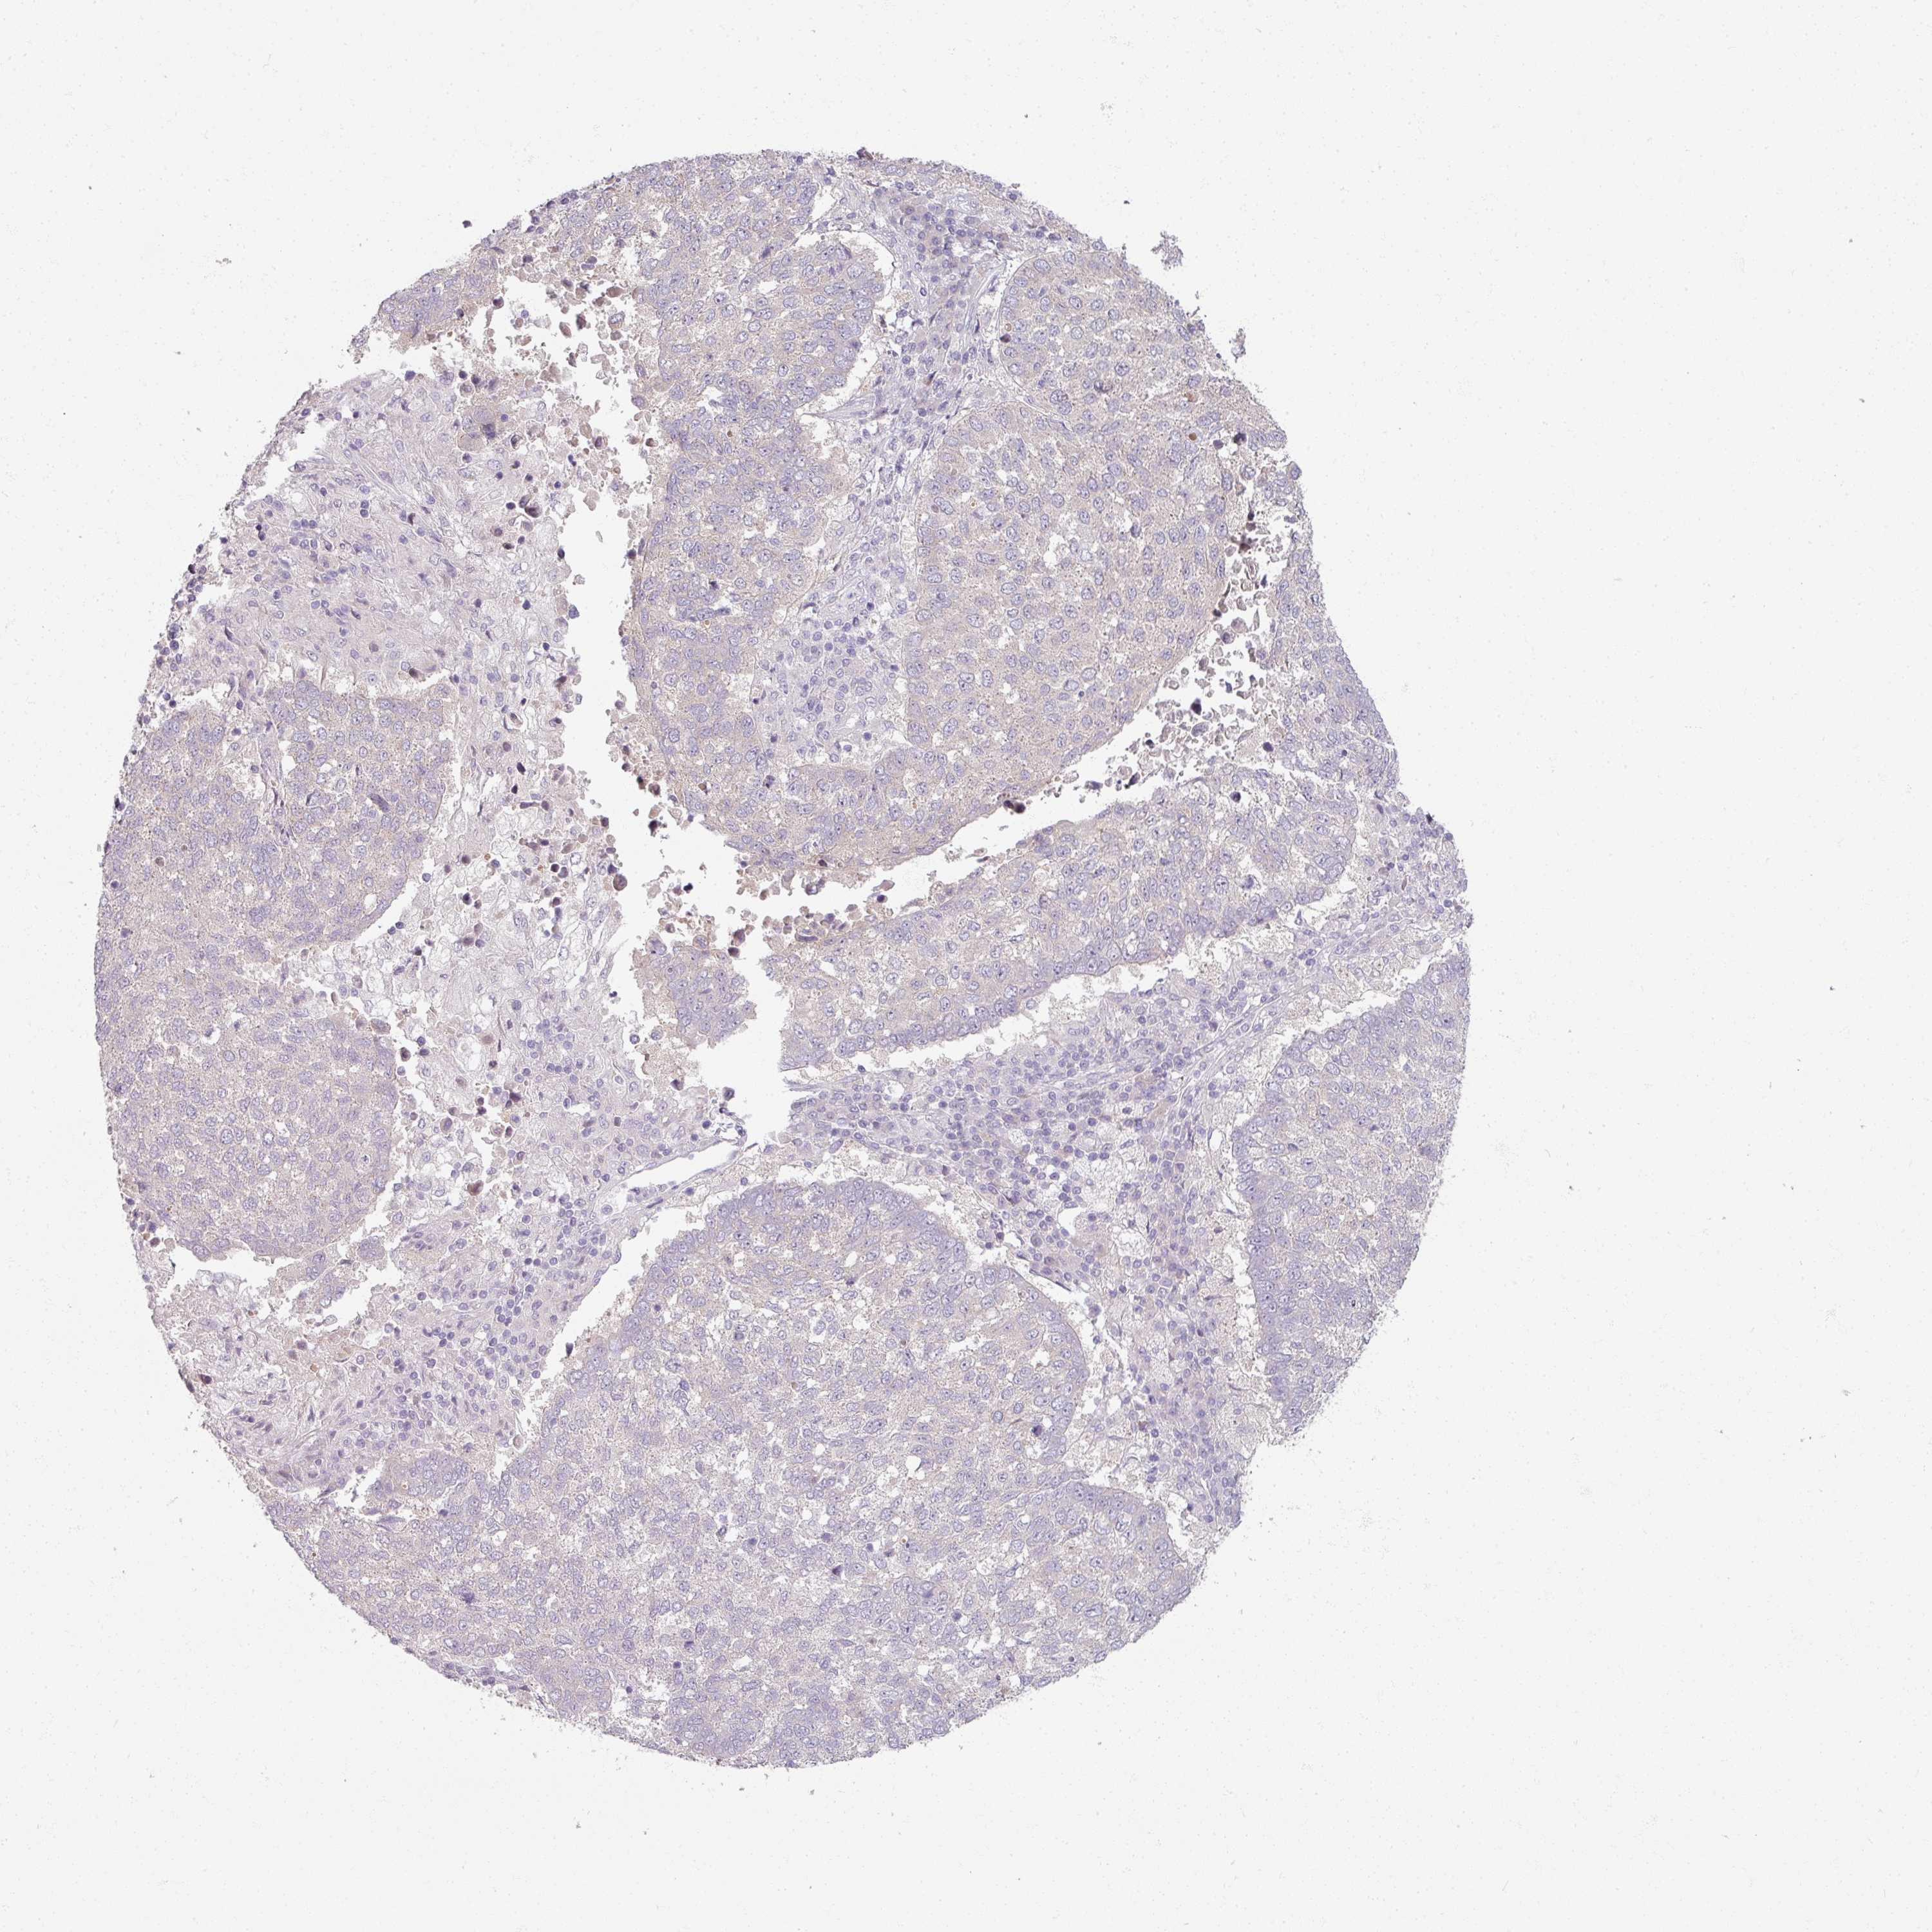

CANCER LUNG CANCER Show tissue menu

LUAD TCGA LUAD VALIDATION LUSC TCGA LUSC VALIDATION PROTEIN LUAD CPTAC PROTEIN LUSC CPTAC PROTEIN EXPRESSION